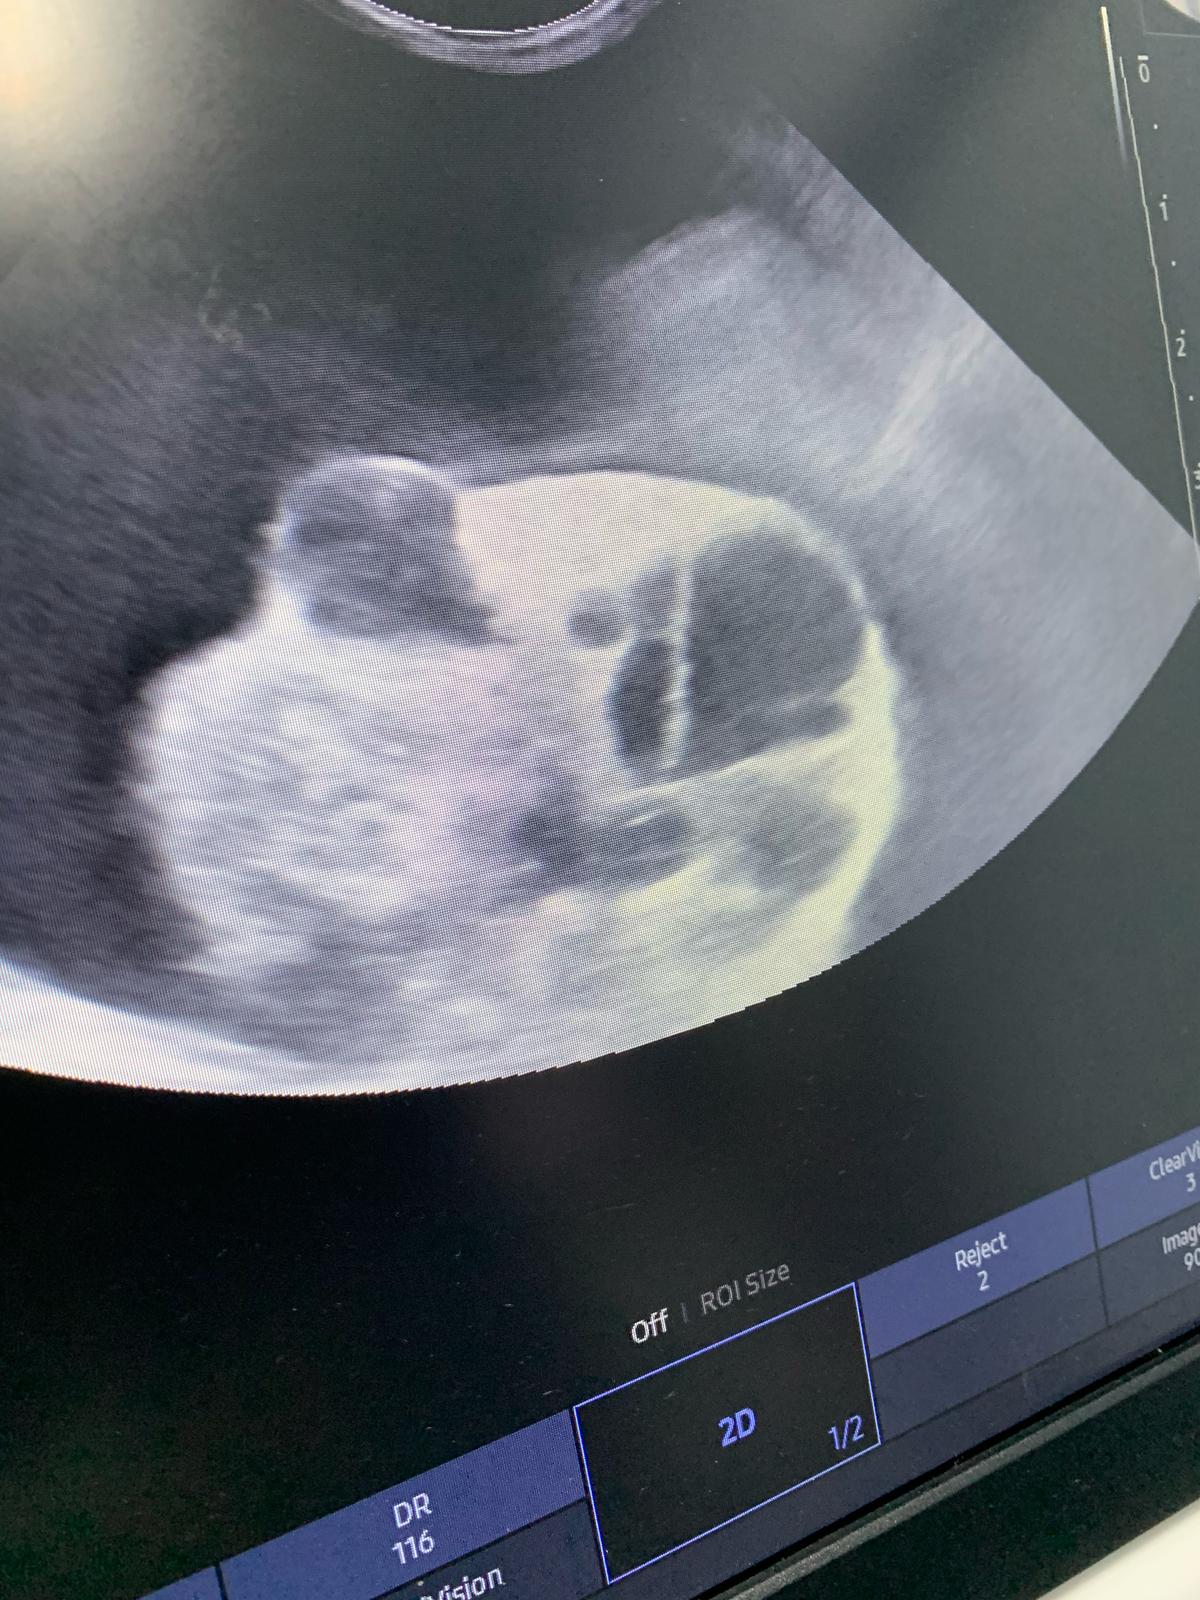

10.33am: dr d show me an u/s says don don kidney r the worst she had ever see, full of cysts for both kidneys. She remember Raichu so this family has a bad gene of cysts issue pass down. Don fluid r ard the kidneys, not the same as norm cats who had fluid ard the intestine, she said dr ym says it’s the same as last time, so she is confident of tapping, will do it away fr the kidneys. But the tapping won’t stop the cyst from leaking again. (Dr d mention more them twice that cysts r painful) noted that the tapping is more benefial to don don, only damage is my pocket) and the coming back is next time biz (maybe monthly tapping see how first).

11.38am: seen dr nally. She did hear mur mur. 3.48kg – gain 220g in 3 days, gain fluid. Taken a quick u/s scan, his cysts are all surrounded by a big ball of fluid (scary as in not sure is it the kidney itself, if yes, means the kidney super swell) or ???! N yet there are still some (little) free fluid outside the ball. For both side. Rejected the tapping. Too dangerous, might just burst the kidney/ ball.

Dr told me to go in to see her scan – both kidneys irregular in shape, like got holes like that (pic la, but he got multiple cysts on his kidneys) liver ok.